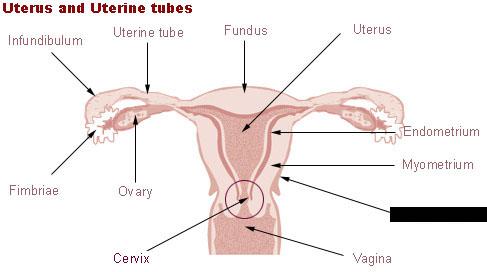

Broad ligament

Cervix

Corpus luteum

Endometrium

Fimbriae

Mature (=Graafian, = antral) follicle

Myometrium

Overian ligament

Ovary

Perimetrium

Primordial/primary/secondary follicle

Round ligament (of uterus)

Uterine (=fallopian) tube

Uterus

Vagina

Vaginal orifice